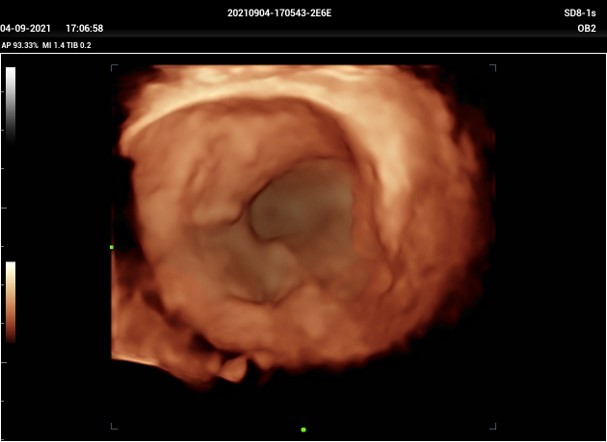

Smart Bladder : Automatické presné vypočítanie objemu močového mechúra. Po priložení volumetrickej brušnej sondy na oblasť močového mechúra a stlačení príslušného tlačítka softvér dokáže sám vyhľadať močový mechúr, tento zobrazí a obkreslí v troch na seba kolmých rovinách. Následne vypočíta objem mechúra. Tento obraz je možné otáčať vo všetkých 3 rovinách.

3D mechúra